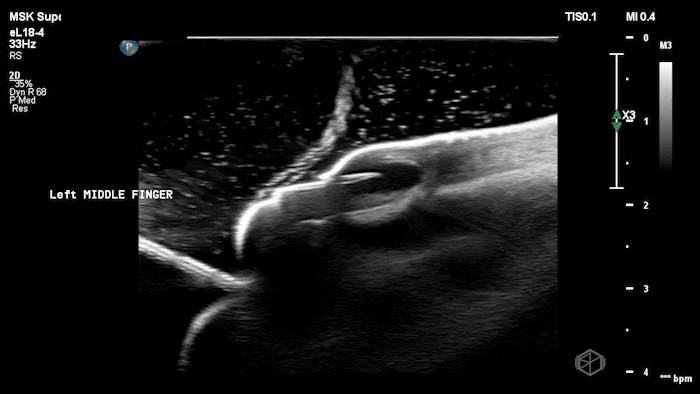

05 - What is being examined and what is the diagnosis?

Phlebitis (no thrombus present to make it thrombophlebitis)